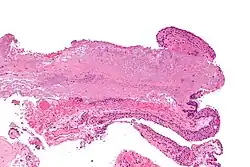

Pterygium in the conjunctiva is characterized by elastotic degeneration of collagen (actinic elastosis[12]) and fibrovascular proliferation. It has an advancing portion called the head of the pterygium, which is connected to the main body of the pterygium by the neck. Sometimes a line of iron deposition can be seen adjacent to the head of the pterygium called Stocker's line. The location of the line can give an indication of the pattern of growth.

The pterygium is composed of several segments:

- Fuchs' Patches (minute gray blemishes that disperse near the pterygium head)

- Stocker's Line (a brownish line composed of iron deposits)

- Hood (fibrous nonvascular portion of the pterygium)

- Head (apex of the pterygium, typically raised and highly vascular)

- Body (fleshy elevated portion congested with tortuous vessels)

- Superior Edge (upper edge of the triangular or wing-shaped portion of the pterygium)

- Inferior Edge (lower edge of the triangular or wing-shaped portion of the pterygium).